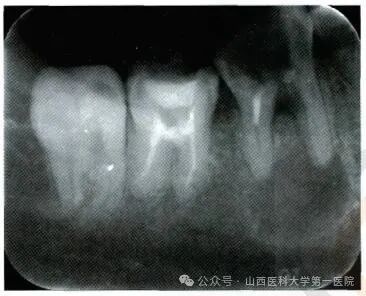

早期筛查:成年人的高发人群或易感人群应自觉进行口腔检查,每3-5年一次,进行视诊、触诊、X线片筛查等,其中X线片是一种简单易行且误诊率较低的方法,可以快速定位疾病。